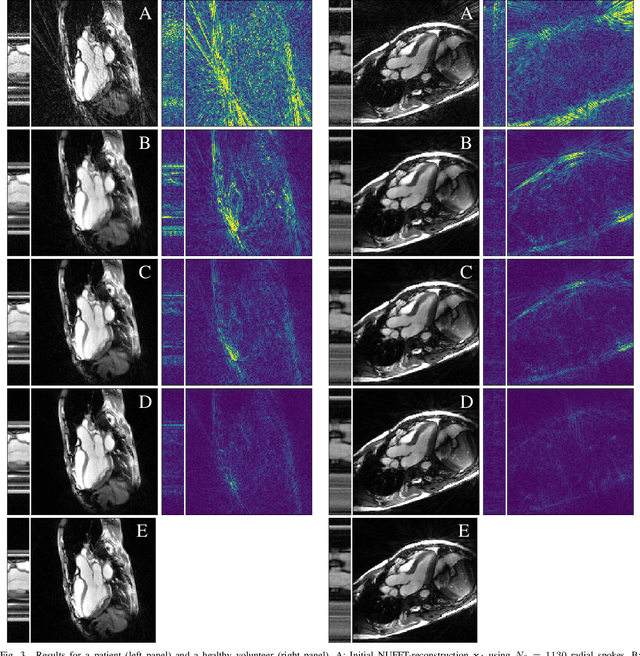

Abstract:Purpose: Iterative Convolutional Neural Networks (CNNs) which resemble unrolled learned iterative schemes have shown to consistently deliver state-of-the-art results for image reconstruction problems across different imaging modalities. However, because these methodes include the forward model in the architecture, their applicability is often restricted to either relatively small reconstruction problems or to problems with operators which are computationally cheap to compute. As a consequence, they have so far not been applied to dynamic non-Cartesian multi-coil reconstruction problems. Methods: In this work, we propose a CNN-architecture for image reconstruction of accelerated 2D radial cine MRI with multiple receiver coils. The network is based on a computationally light CNN-component and a subsequent conjugate gradient (CG) method which can be jointly trained end-to-end using an efficient training strategy. We investigate the proposed training-strategy and compare our method to other well-known reconstruction techniques with learned and non-learned regularization methods. Results: Our proposed method outperforms all other methods based on non-learned regularization. Further, it performs similar or better than a CNN-based method employing a 3D U-Net and a method using adaptive dictionary learning. In addition, we empirically demonstrate that even by training the network with only iteration, it is possible to increase the length of the network at test time and further improve the results. Conclusions: End-to-end training allows to highly reduce the number of trainable parameters of and stabilize the reconstruction network. Further, because it is possible to change the length of the network at test time, the need to find a compromise between the complexity of the CNN-block and the number of iterations in each CG-block becomes irrelevant.

Abstract:In this work, we propose an iterative reconstruction scheme (ALONE - Adaptive Learning Of NEtworks) for 2D radial cine MRI based on ground truth-free unsupervised learning of shallow convolutional neural networks. The network is trained to approximate patches of the current estimate of the solution during the reconstruction. By imposing a shallow network topology and constraining the $L_2$-norm of the learned filters, the network's representation power is limited in order not to be able to recover noise. Therefore, the network can be interpreted to perform a low dimensional approximation of the patches for stabilizing the inversion process. We compare the proposed reconstruction scheme to two ground truth-free reconstruction methods, namely a well known Total Variation (TV) minimization and an unsupervised adaptive Dictionary Learning (DIC) method. The proposed method outperforms both methods with respect to all reported quantitative measures. Further, in contrast to DIC, where the sparse approximation of the patches involves the solution of a complex optimization problem, ALONE only requires a forward pass of all patches through the shallow network and therefore significantly accelerates the reconstruction.

Abstract:In this paper we present a generalized Deep Learning-based approach for solving ill-posed large-scale inverse problems occuring in medical image reconstruction. Recently, Deep Learning methods using iterative neural networks and cascaded neural networks have been reported to achieve state-of-the-art results with respect to various quantitative quality measures as PSNR, NRMSE and SSIM across different imaging modalities. However, the fact that these approaches employ the forward and adjoint operators repeatedly in the network architecture requires the network to process the whole images or volumes at once, which for some applications is computationally infeasible. In this work, we follow a different reconstruction strategy by decoupling the regularization of the solution from ensuring consistency with the measured data. The regularization is given in the form of an image prior obtained by the output of a previously trained neural network which is used in a Tikhonov regularization framework. By doing so, more complex and sophisticated network architectures can be used for the removal of the artefacts or noise than it is usually the case in iterative networks. Due to the large scale of the considered problems and the resulting computational complexity of the employed networks, the priors are obtained by processing the images or volumes as patches or slices. We evaluated the method for the cases of 3D cone-beam low dose CT and undersampled 2D radial cine MRI and compared it to a total variation-minimization-based reconstruction algorithm as well as to a method with regularization based on learned overcomplete dictionaries. The proposed method outperformed all the reported methods with respect to all chosen quantitative measures and further accelerates the regularization step in the reconstruction by several orders of magnitude.